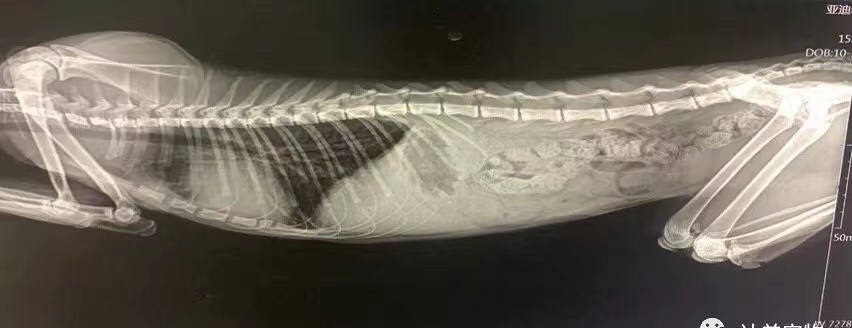

和主人基本沟通后为钢弹做了基本传染病筛查、血液生化检查、血液常规检查及X光检查,初步诊断为胆汁淤积性黄疸,胆囊炎、胆管炎、疑似传染性腹膜炎(需进一步鉴别诊断)。

X光检查钢蛋的肝胆状况